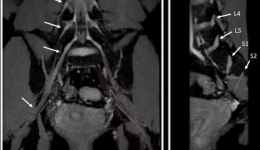

近期,我院放射科医技护团队在郭依廷主任带领下,成功开展核磁共振前沿成像技术-腰骶丛核磁共振神经成像(MRN,MRNeurography),进一步提升了我院影像诊疗技术,填补了在该领域的空白。腰骶丛MRN是一种无创性成像技术,用于腰骶丛神经的评估。由于其...

近期,我院放射科医技护团队在郭依廷主任的领导下,使用联影uMR7803.0T超高端磁共振,成功开展三叉神经磁共振成像(MRI)新技术,进一步提升了放射科医疗服务能力,填补了在该领域的空白,为临床诊疗带来了更为精准、高效的诊断方式,让更多患者受...